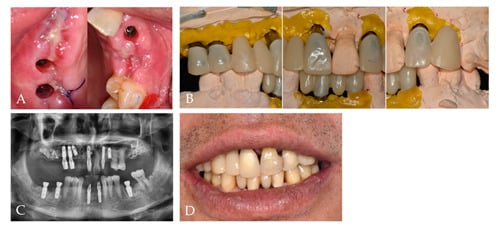

2. Case Report